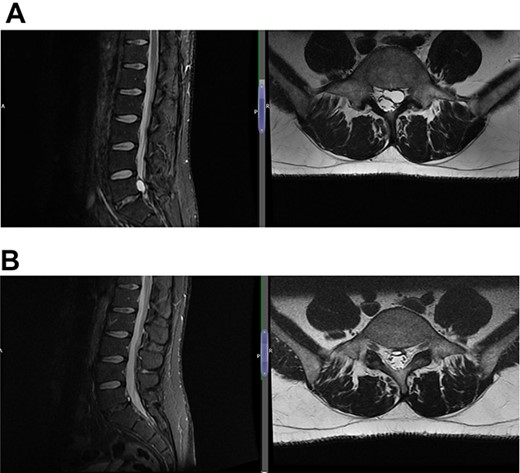

(A) Case 2—initial MRI shows a slightly unusual abnormality associated with the L5-S1 compressing the left transiting S1 nerve root and is almost certainly a fragment of extruded/sequestered disc, and (B) case 2—updated MRI shows a significant decrease in the previously seen cystic lesion at L5-S1 level now measuring 4 mm (AP diameter, previously 11 mm).